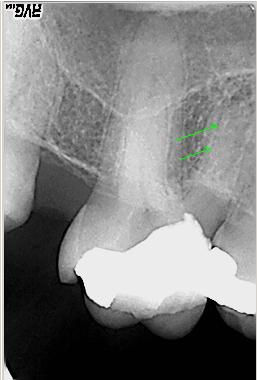

Distalexzentische Projektion

Distalexzentische Projektion mit zweitem Parodontalspalt in der mesiobuccalen Wurzel als deutlicher Hinweis für ein zusätzliches viertes Kanalsystem

Die gleiche Situation vergrößert. Der grüne Pfeil zeigt den winzigen oftmals nur zu erahnenden bzw. zu ertastenden Eingang von MB2

Mit einer 10er Handfeile wird der MB2 Kanaleingang dargestellt (grüner Pfeil). Der rote Pfeil zeigt die zu erwartende Lage des Kanaleinganges nach „Aufrichten“ des Kanales und zwar mesial der Verbindungslinie MB1-P